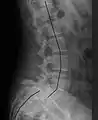

X-ray of measurement of spondylolisthesis at the lumbosacral joint, being 25% in this example

Classification by degree of the slippage, as measured as percentage of the width of the vertebral body:[14] Grade I spondylolisthesis accounts for approximately 75% of all cases.[6]

- Grade I: 0–25%

- Grade II: 25–50%

- Grade III: 50–75%

- Grade IV: 75–100%

- Grade V: greater than 100%